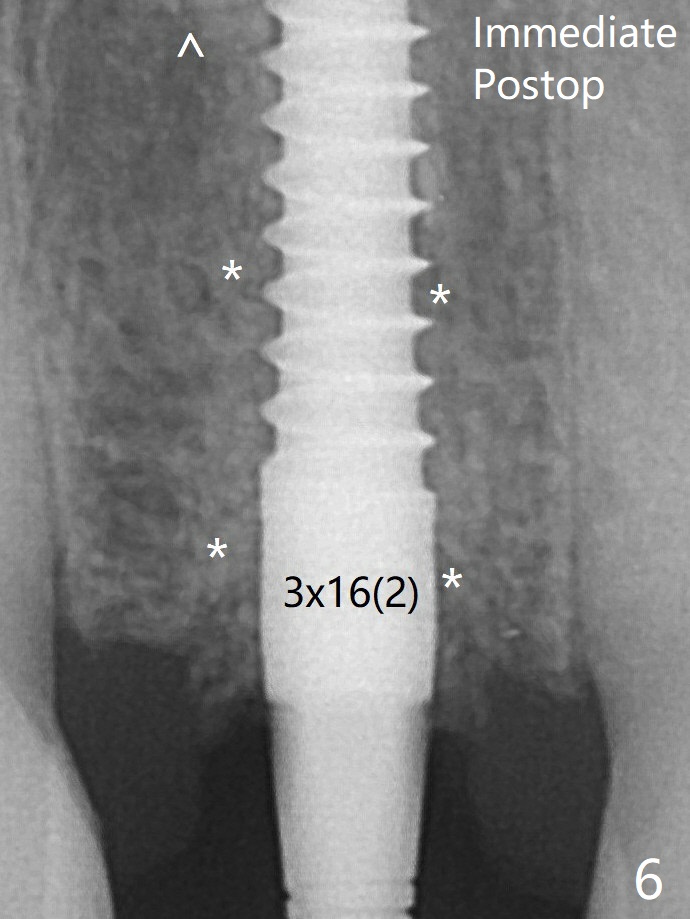

After adjustment of the trajectory of osteotomy (Fig.5), a 3x16(2) mm 1-piece implant is placed within normal limit (10-15 Ncm, Fig.6)).  In fact bone graft is placed before (^ arrowhead; to repair apical buccal plate perforation) and after (*) implantation.  The bone graft becomes more organized 3 months postop (Fig.9).术后三个月骨粉形态改变(图九,与图六对比)。